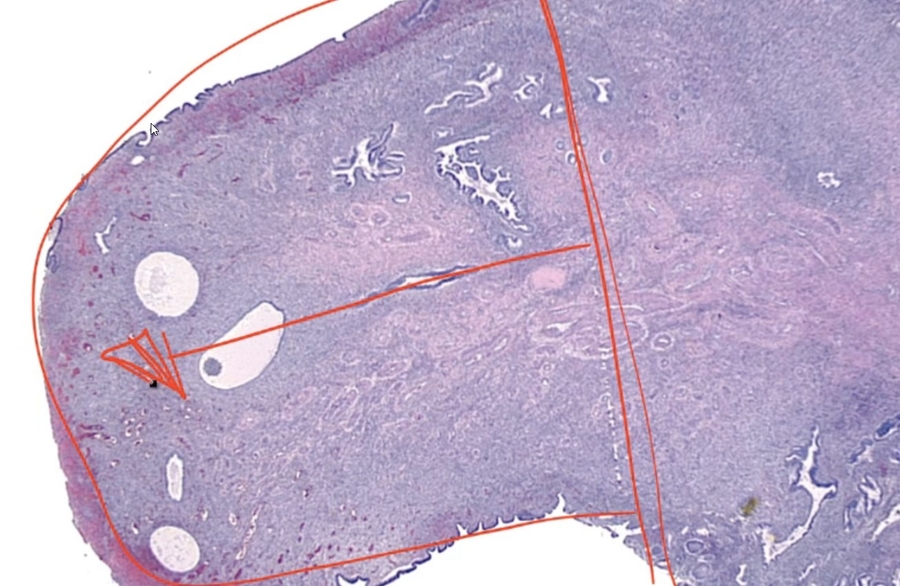

Adenosis of vagina:

Adenosis

_ Focal persistence of columnar epithelium in the upper vagina.

During development, squamous epithelium from lower 1/3 (urogenital sinus) of the vagina grows upward to replace columnar epithelium lining of upper 2/3 of vagina (mullerian ducts)

_In utero exposure to diethylstilbestrol (DES) is a major risk factor for adenosis of the vagina.